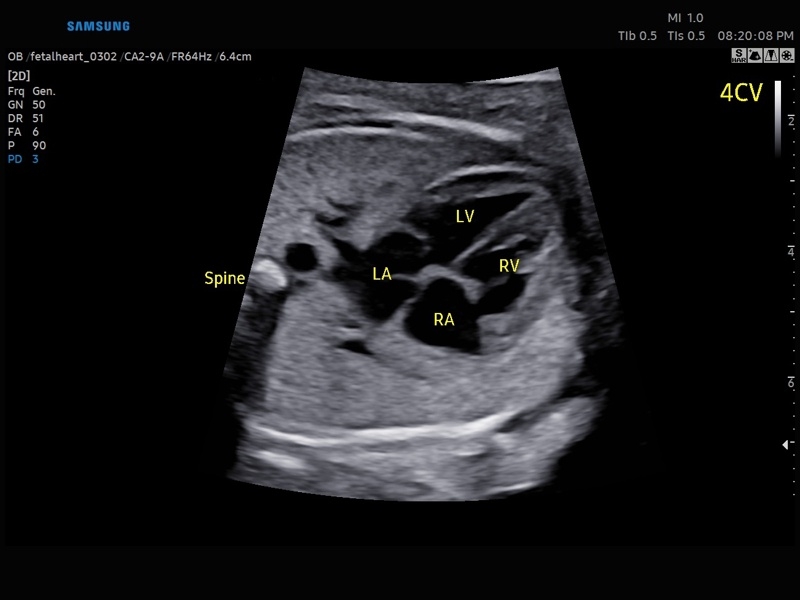

• Сердце плода:измерения в В-режиме (отношение площади сердца и грудной клетки), измерения в М-режиме (толщина межжелудочковой перегородки в диастолу, конечнодиастолический размер левого желудочка, толщина задней стенки левого желудочка в диастолу, толщина межжелудочковой перегородки в систолу, размер левого желудочка в систолу, толщина задней стенки левого желудочка в систолу, внутренний размер правого желудочка в диастолу), измерения в режиме спектрального допплера (легочный ствол, артериальный проток, нижняя полая вена, венозный проток, восходящая аорта, нисходящая аорта, трансмитральный кровоток, митральная регургитация, трикуспидальный кровоток, трикуспидальная регургитация, индекс преднагрузки, ЧСС).

• МодульSTIC- объемная динамическая визуализация сердца плода.

• M - одномерный режим для исследования сердца, анатомический М-режим (необходим кардиопакет), CM - цветной М-режим (необходим кардиопакет).

• Кардиопакет: тканевый допплер (TDI) + анатомический М-режим + цветной М-режим (CM) + программное обеспечение.

• Кардиологический пакет с функцией StressEcho